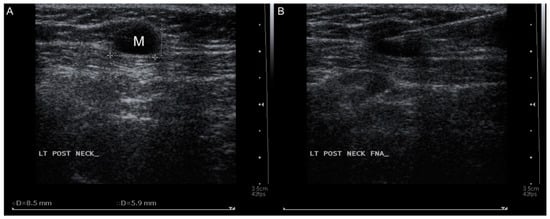

2. Case Presentation